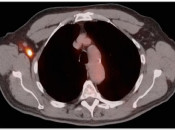

Patient Preparation (Plasma Glucose Level, Insulin, Exercise):

Essentially, elevated plasma glucose will compete with FDG (a glucose analog), decreasing tumoral uptake.  Elevated glucose also stimulated insulin production, driving glucose (and FDG) into muscle.  Recent strenuous exercise also drives FDG into skeletal muscle.   Ultimately, excessive skeletal muscle uptake, irrespective of etiology, both decreases available FDG for tumor uptake (decreasing tumor SUV) and potentially obscures lesions within or adjacent to this hypermetabolic muscle. [FIG. 1]   [FIG. 2]